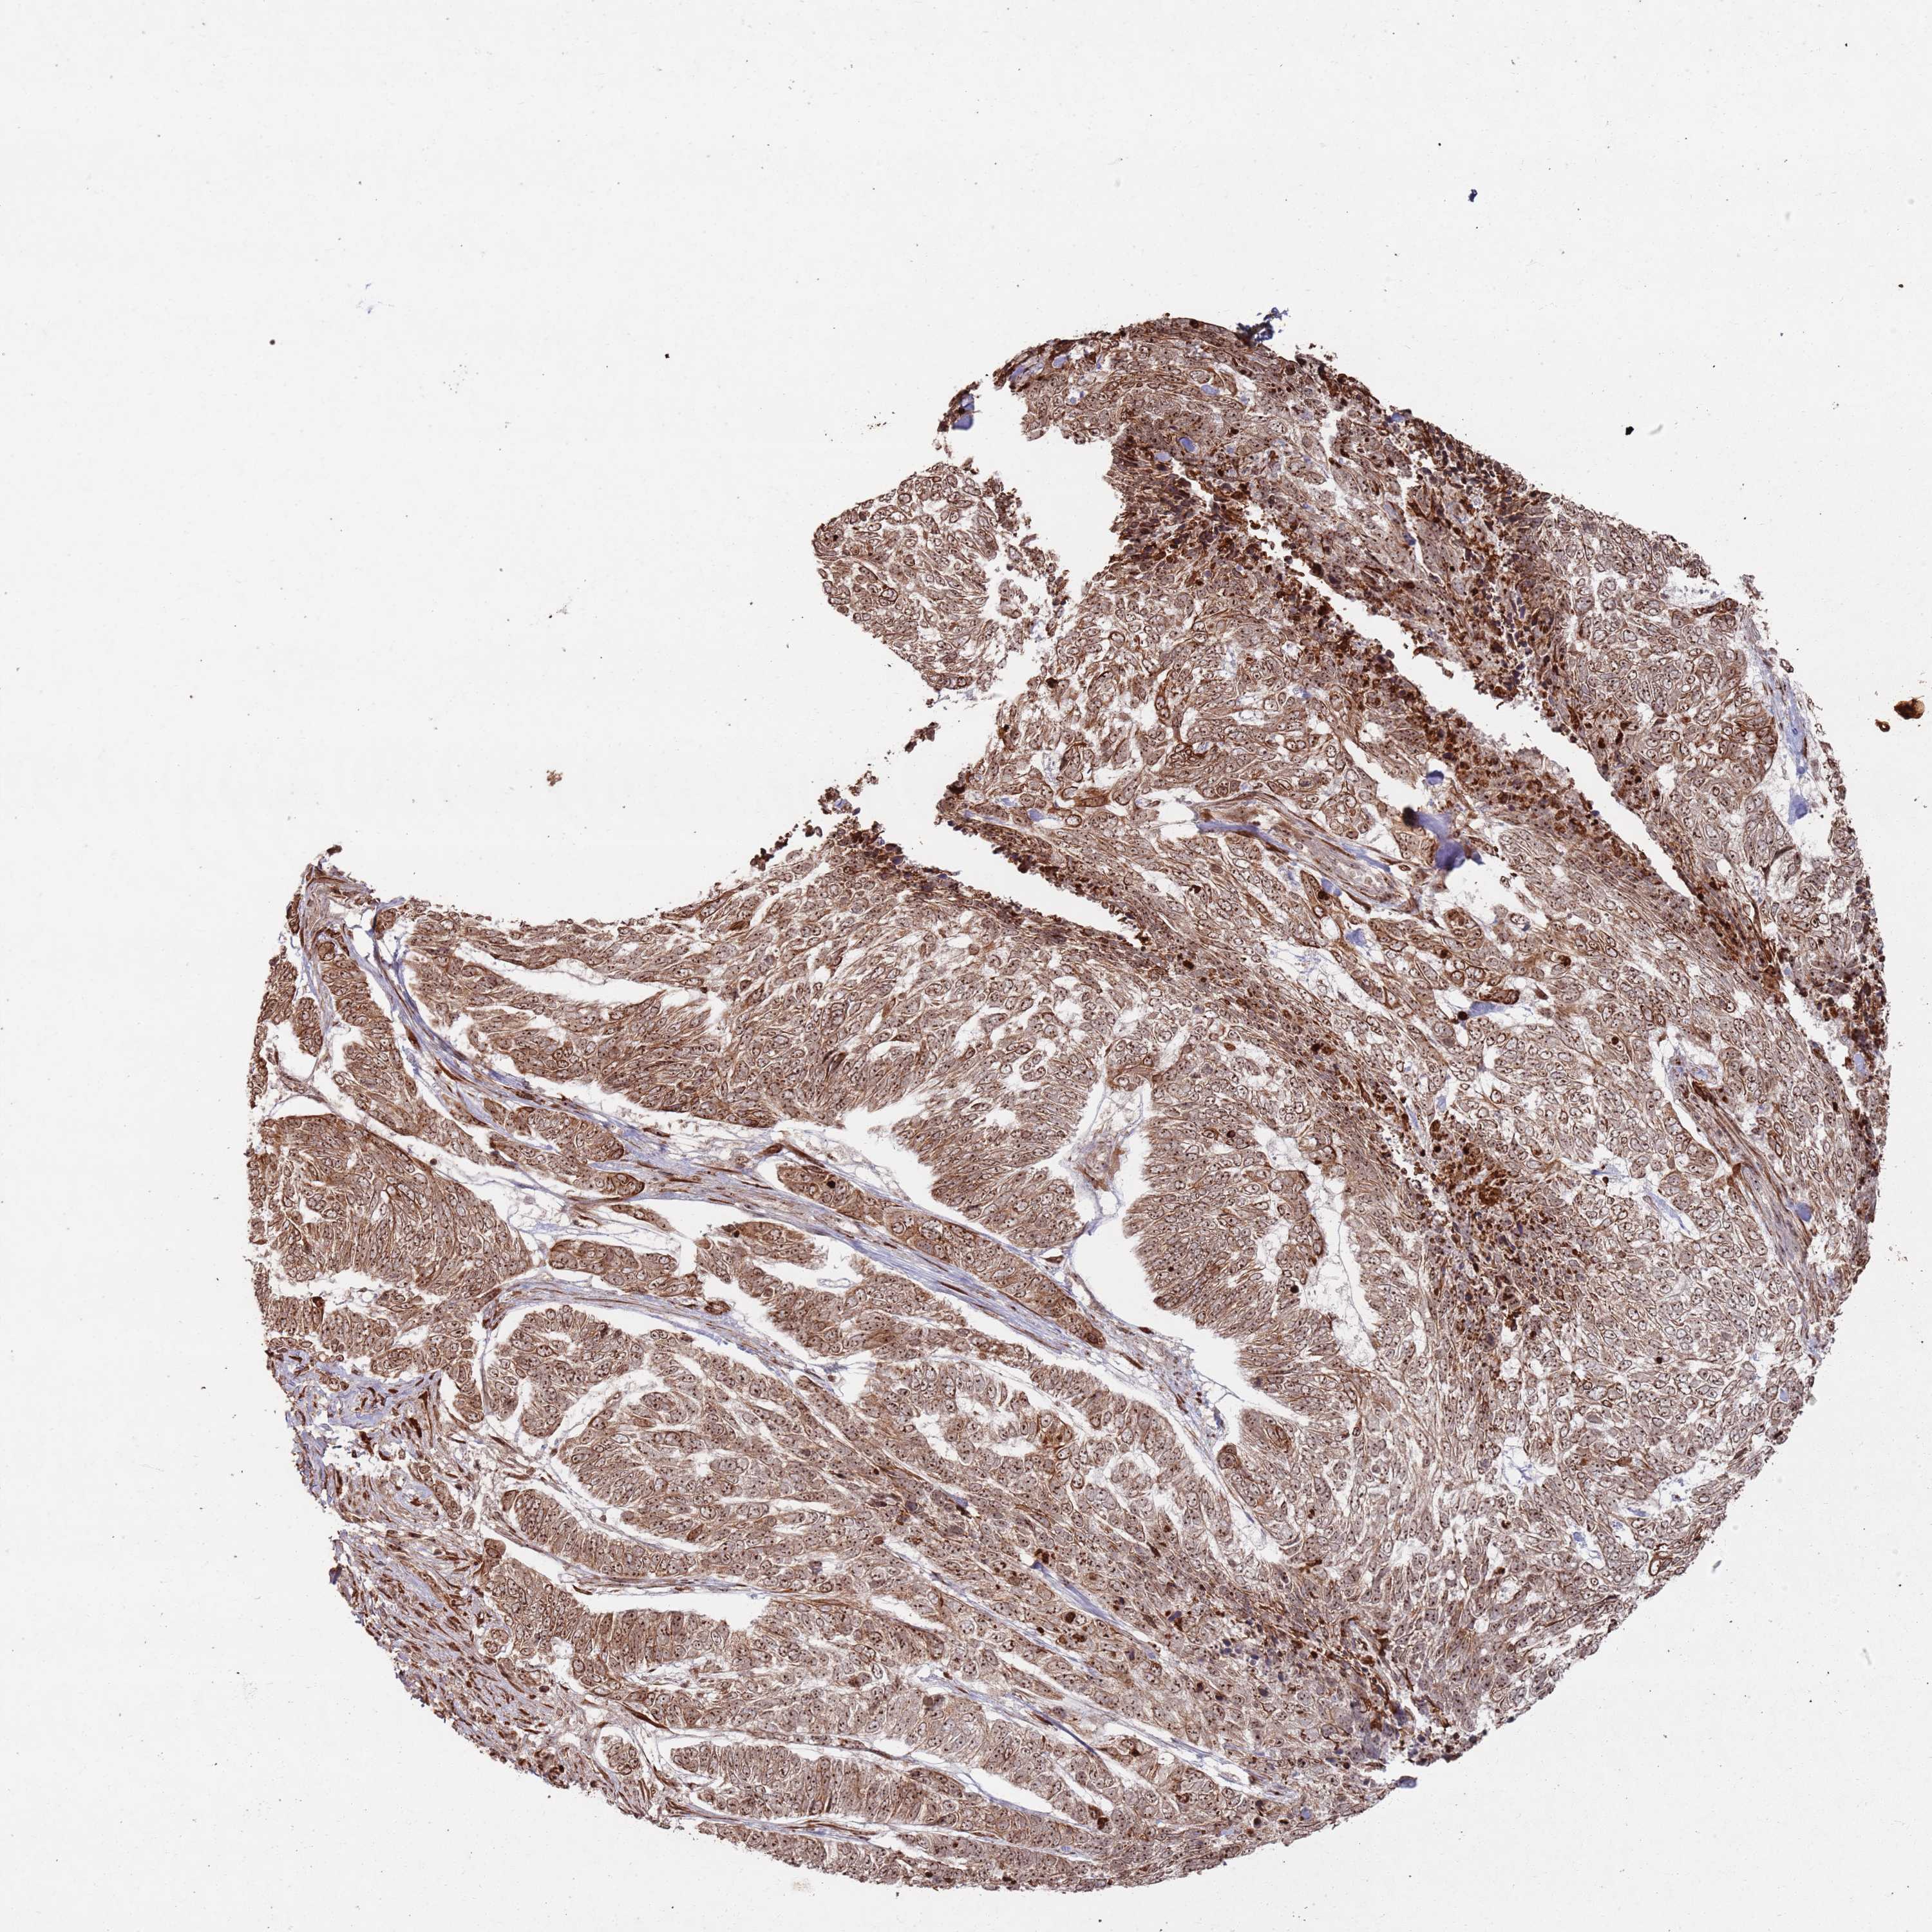

SKIN CANCER - Protein expressioni

A mouse-over function shows sample information and annotation data. Click on an image to view it in a full screen mode. Samples can be filtered based on level of antibody staining by selecting one or several of the following categories: high, medium, low and not detected. The assay and annotation is described here.

Antibody stainingi

Antibody staining in the annotated cell types in the current human tissue is reported as not detected, low, medium, or high, based on conventional immunohistochemistry profiling in selected tissues. This score is based on the combination of the staining intensity and fraction of stained cells.

Each image is clickable and will lead to virtual microscopy that enables deeper exploration of all samples and also displays staining intensity scores, fraction scores and subcellular localization as well as patient and tissue information for each sample.

Antibody HPA045830

Staining

High

Medium

Low

Not detected

Intensity

Strong

Moderate

Weak

Negative

Quantity

>75%

75%-25%

<25%

None

Location

Nuclear

Cytoplasmic/membranous

Cytoplasmic/membranous,nuclear

Basal cell carcinoma

Squamous cell carcinoma, NOS

Squamous cell carcinoma, metastatic, NOS

Squamous cell carcinoma in situ, NOS